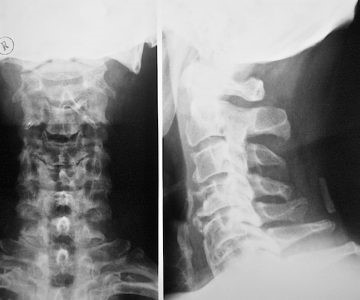

На первоначальном этапе огромное значение имеет тщательный осмотр и внимательный опрос пациента – это позволит избежать потери драгоценного времени и средств на проведение излишних исследований. Далее в обязательном порядке следует рентгенография.

До сегодняшнего дня именно этот вид исследования позволяет получить самую достоверную информацию относительно патологий в позвоночнике.

Рентгенологическое исследование проводится в разных проекциях – прямой и нескольких боковых. Снимок позволяет увидеть аномально низкую высоту хрящей между позвонками, уменьшенное расстояние между позвоночными отростками и разрастание костной ткани.

Во время рентгена больному в обязательном порядке нужно предложить открыть рот, поскольку при таком положении на снимке особенно наглядно видны патологии шейного отдела позвоночника.